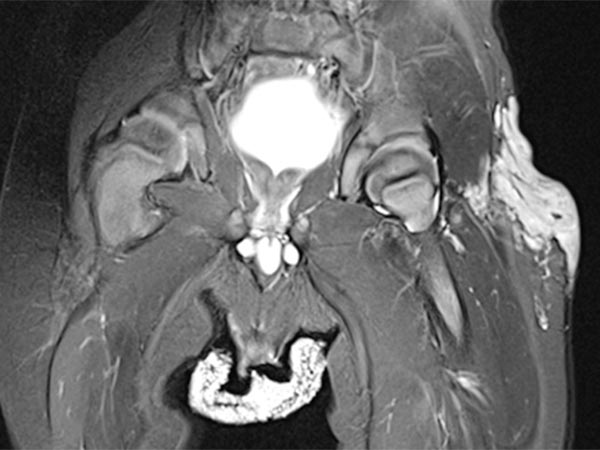

Die koronare, T2-gewichtete, fettgesättigte MRT zeigt den Tumor in der linken Leiste homogen stark hyperintens (13. Lebensmonat) und klar solide. Nebenbefundlich die durchnässte Windel, ebenfalls mit hoher Signalintensität.

Gleiche MRT-Sequenz, koronare Schichtführung. Der Tumor liegt nicht nur epifaszial, sondern zeigt auch eine geringe Ausdehnung nach subfaszial unter die Fascia lata in die Glutealmuskulatur. Damit klar infiltratives Verhalten.

Koronare, T1-gewichtete, fettgesättigte MRT nach Kontrastmittelgabe. Der Tumor zeigt ein homogenes, starkes Enhancement. Daneben zwei zentrale Flow-voids als Zeichen der starken arteriellen Perfusion.

Kontrastmittelunterstützte, dynamische MR-Angiographie (koronare Schichtführung).

30 s nach KM-Injektion in der früharteriellen Phase kommt es zu einem sofortigen, frühen Enhancement des Tumors in der linken Leiste.

41 s nach KM-Injektion in der spätarteriellen Phase kommt es zu einem weiteren, eher diffusen, starken Enhancement des Tumors („tumor-blush“) in der linken Leiste, entsprechend einem soliden Gefäßtumor.

57 s nach KM-Injektion in der frühen venösen Phase reichert der gesamte Tumor weiterhin stark an. Es kontrastiert sich jetzt auch eine im Seitenvergleich stark erweiterte frühe Drainagevene. Durch die starke Tumorperfusion mit erhöhtem venösen Abstrom hat sich die venöse Drainage (Venae iliacae links) dilatiert.

130 s nach KM-Injektion in der späten Phase bleibt das starke Enhancement des Tumors in der linken Leiste erhalten, kein frühes „wash-out“. Auch die erweiterte venöse Drainage über die linken Iliakalvenen kontrastiert nach wie vor.